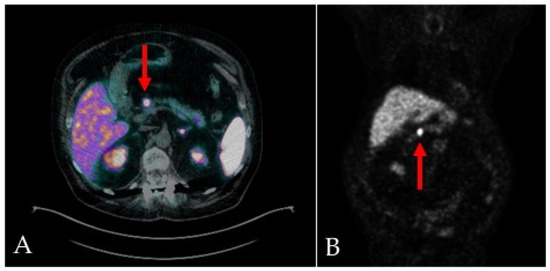

2. Case-Report